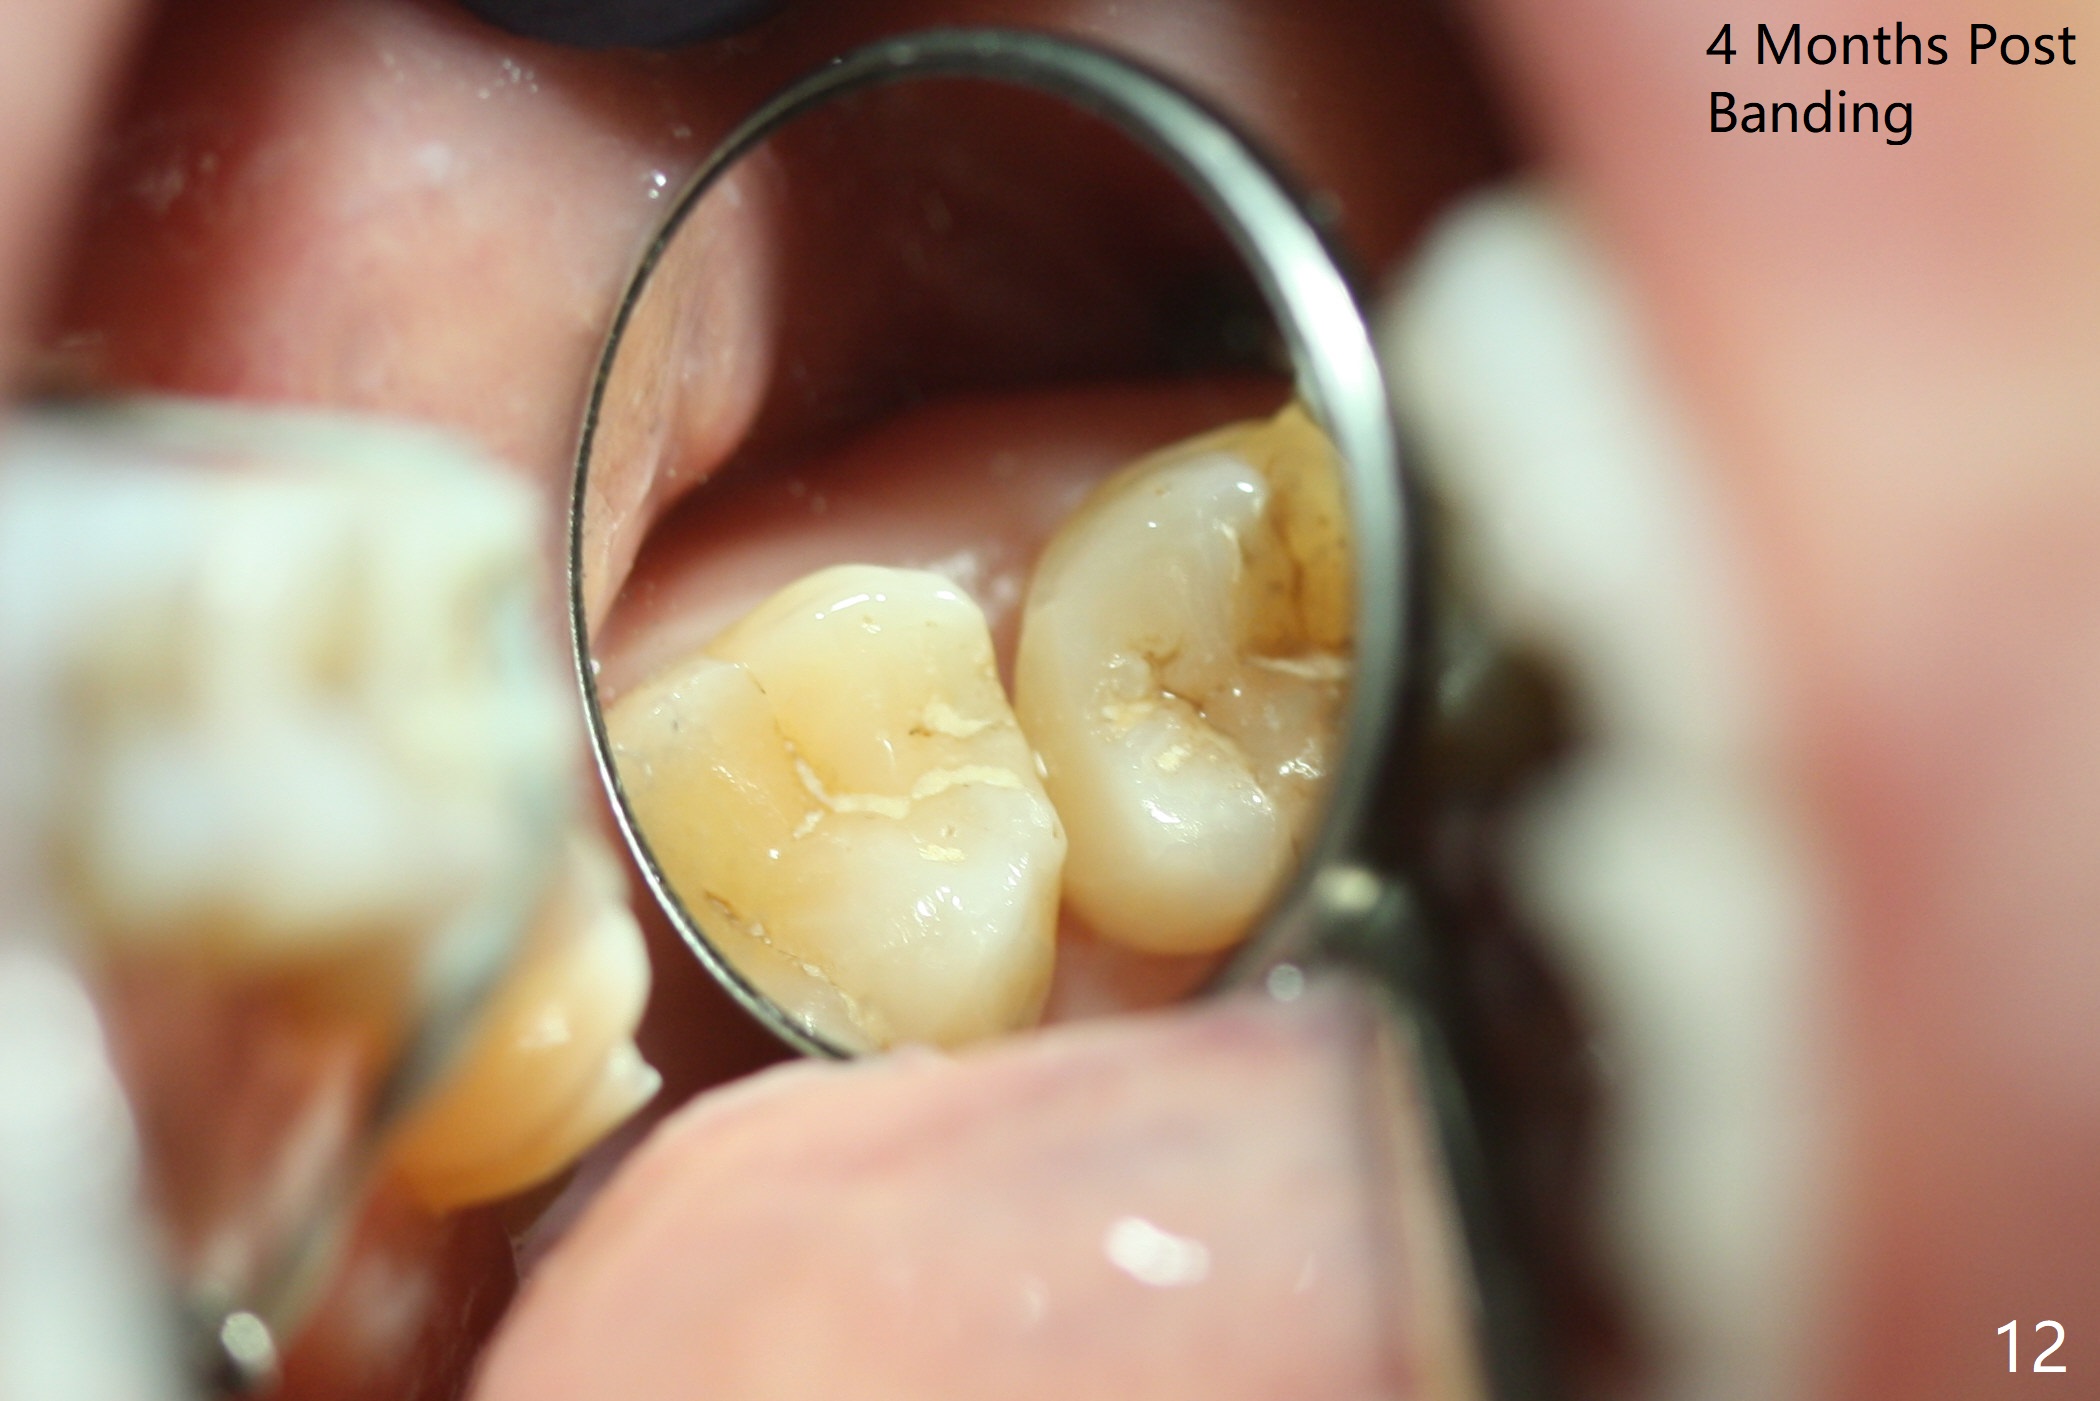

It looks as if the tooth #3 is blocked by the neighboring teeth. The proximal surfaces are reduced 1.5 months post orthodontic intrusion. Fourteen days later, the gap exists distal (Fig.10 *). It appears that the power chains placed on the natural groove of the tooth (white line) mesializes the tooth. Then the power chains are placed mesial to the mesiopalatal cusp by placing 2 of composite (Fig.11); one month later, the distal gap closes (Fig.12). The patient feels less pressure against the teeth anterior to the tooth #14. At the same time, the latter appears to have been intruded. The tooth appears to have been intruded radiographically 4 months post retraction (Fig.13).